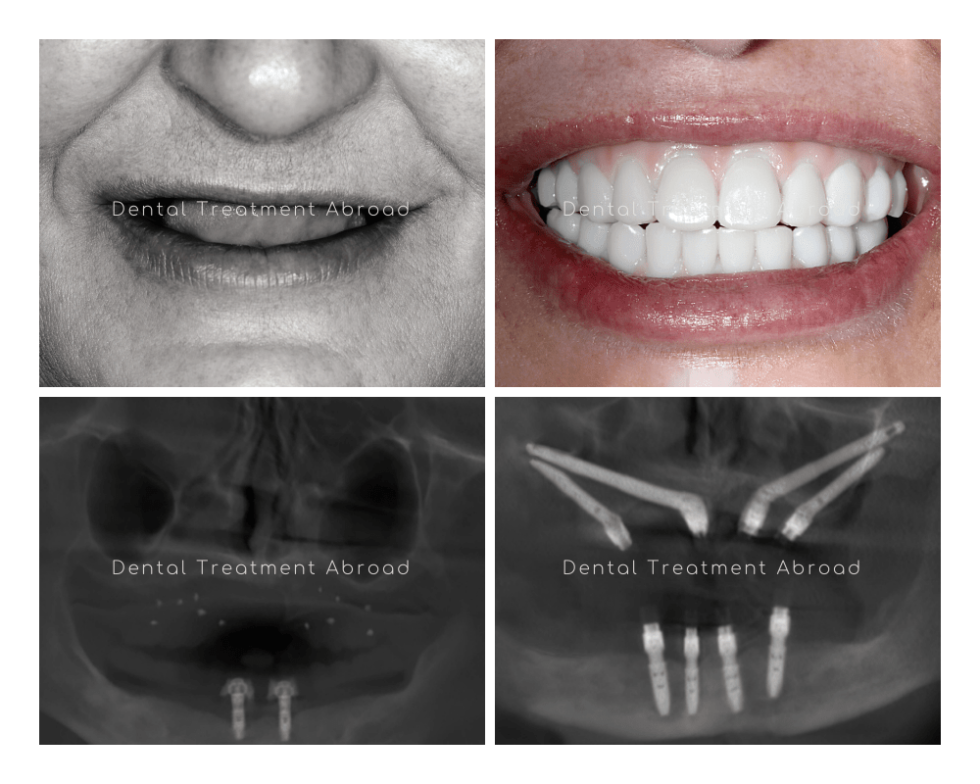

From www.facialart.com

Solutions for Patients with Severe Bone Loss Who Want Dental Implants What Causes Bone Loss After Dental Implants Damage to the tooth can be caused by various etiological factors like periodontal disease, abscess formation, trauma, or vertical. A bone grafting procedure increases the amount of bone in an area of the jaw where there is bone loss or where there is a need for additional support. Infectious disease that causes inflammation of the surrounding gum and bone of. What Causes Bone Loss After Dental Implants.

From www.dentaltreatmentinspain.co.uk

Dental Implant Solutions for Bone Loss Greatest Experts in Spain What Causes Bone Loss After Dental Implants Damage to the tooth can be caused by various etiological factors like periodontal disease, abscess formation, trauma, or vertical. Infectious disease that causes inflammation of the surrounding gum and bone of an already. This allows the surgeon to place. It develops due to chronic inflammation at the site of the implant. A bone grafting procedure increases the amount of bone. What Causes Bone Loss After Dental Implants.